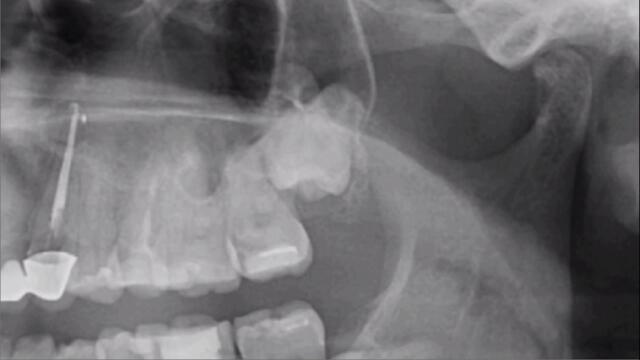

Гледай След екстракцията на мъдрец усещането какво е!? А ако е и ретениран е още по-сериозно, видео качено от mentos, във Videoclip.bg - видео споделяне за всички българи!